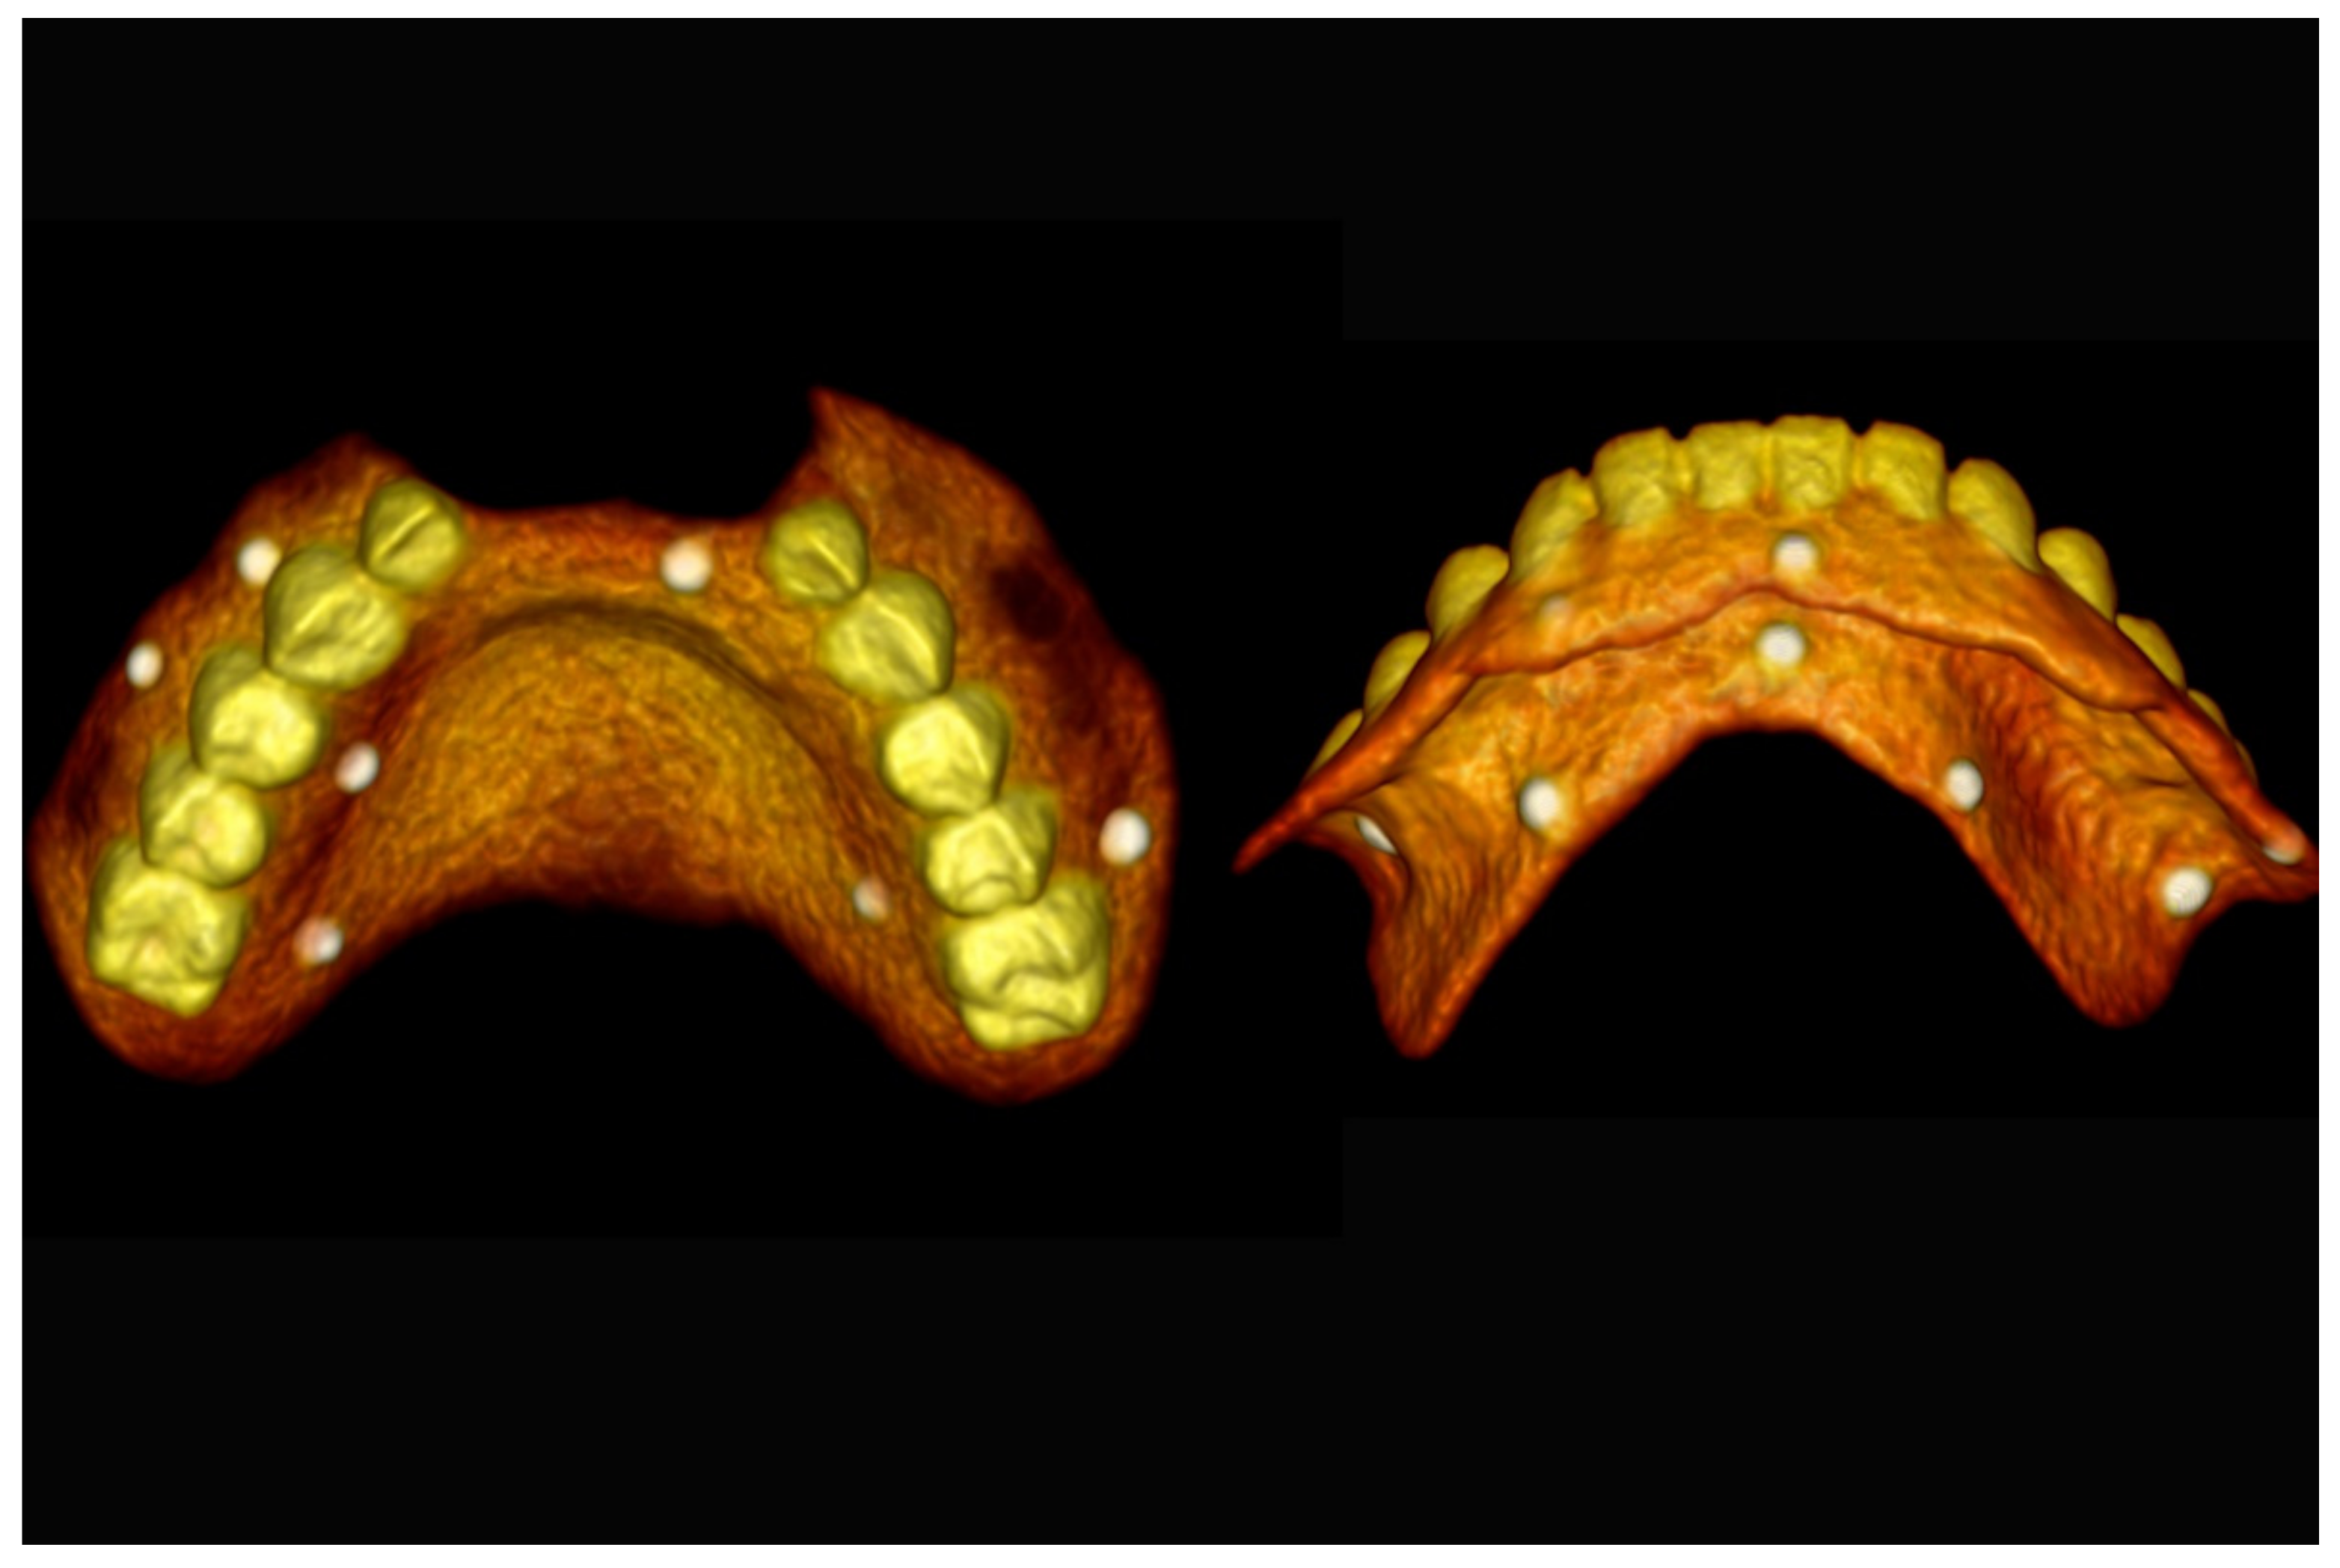

Figure 16.

Three-dimensional (3D) CBCT scan images with the patient wearing the planned prosthesis.

Figure 17.

Three-dimensional (3D) CBCT scan images of the prosthesis equipped with integrated radiopaque reference spheres scanned separately.

Figure 18.

Three-dimensional (3D) planning of the number, the diameter and the axis of dental implants with respect to the design of the final virtual maxillary prosthesis.

Figure 19.